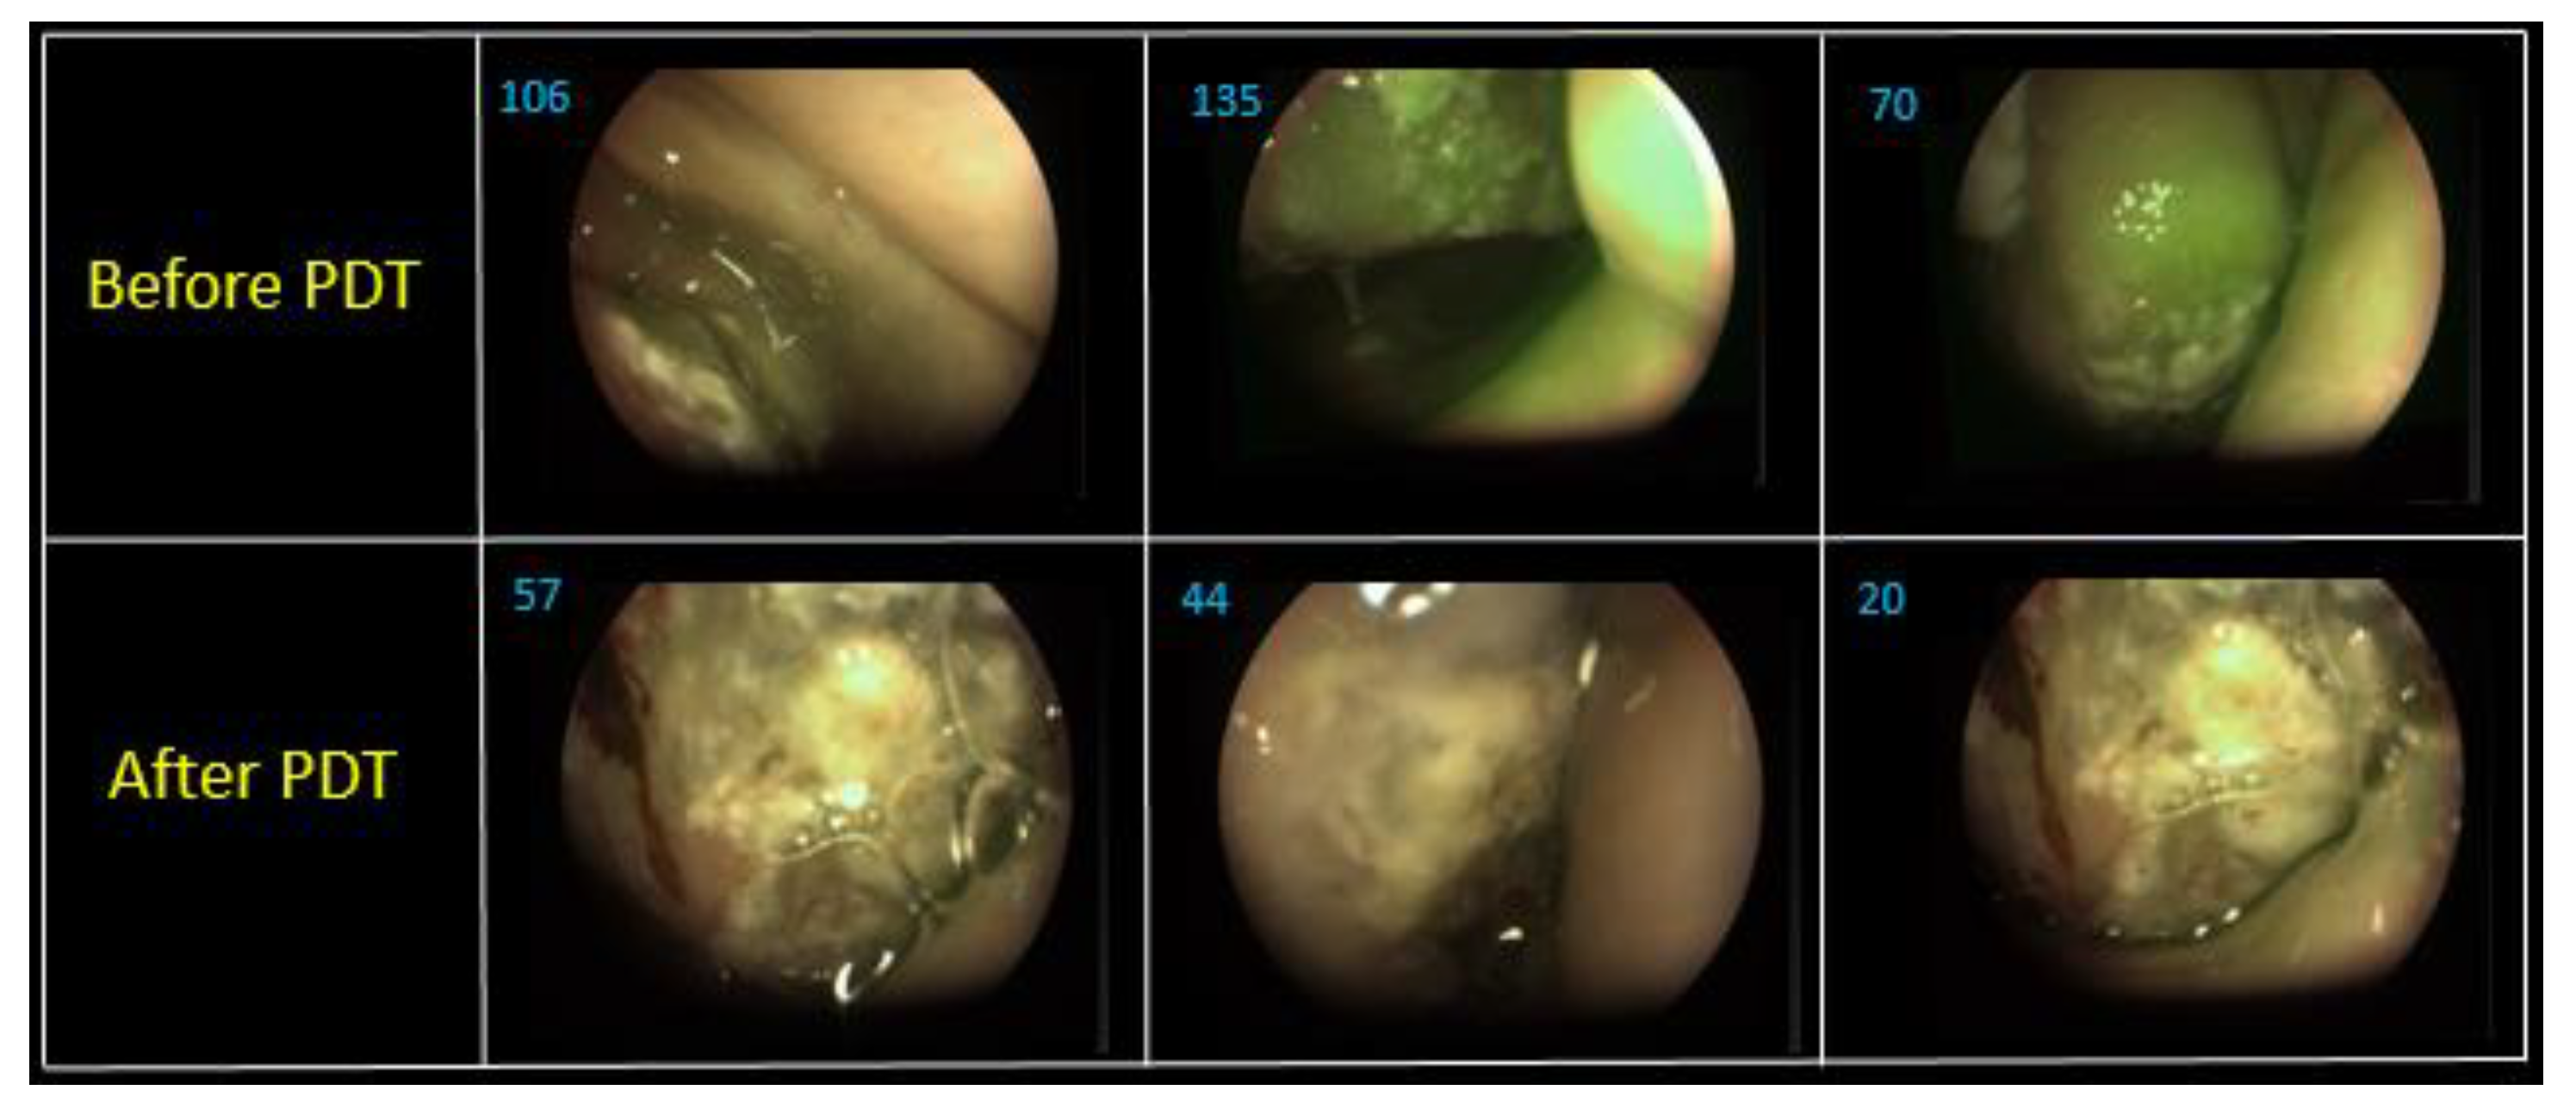

A pathohistological analysis of the biological tissue taken from the tumor site of the right vocal cord is displayed on the Figure 6 and Figure 7.

A histological analysis showed squamous cell carcinoma, G2, before PDT (Figure 6). The microscopic analysis of biopsy sample demonstrated changes in the tumor cells with paretic plethora of the blood vessels of the microvasculature with the formation of blood clots after PDT (Figure 7a,b). There is a positive dynamic observation in the form of complete regression of the tumor.

Figure 6. Moderately differentiated squamous cell carcinoma, G2; staining with hematoxylin-eosin, *100 magnification.

Figure 7. Moderately differentiated squamous cell carcinoma, G2, after PDT; staining with hematoxylin-eosin: (a) *400 magnification; (b) *100 magnification.